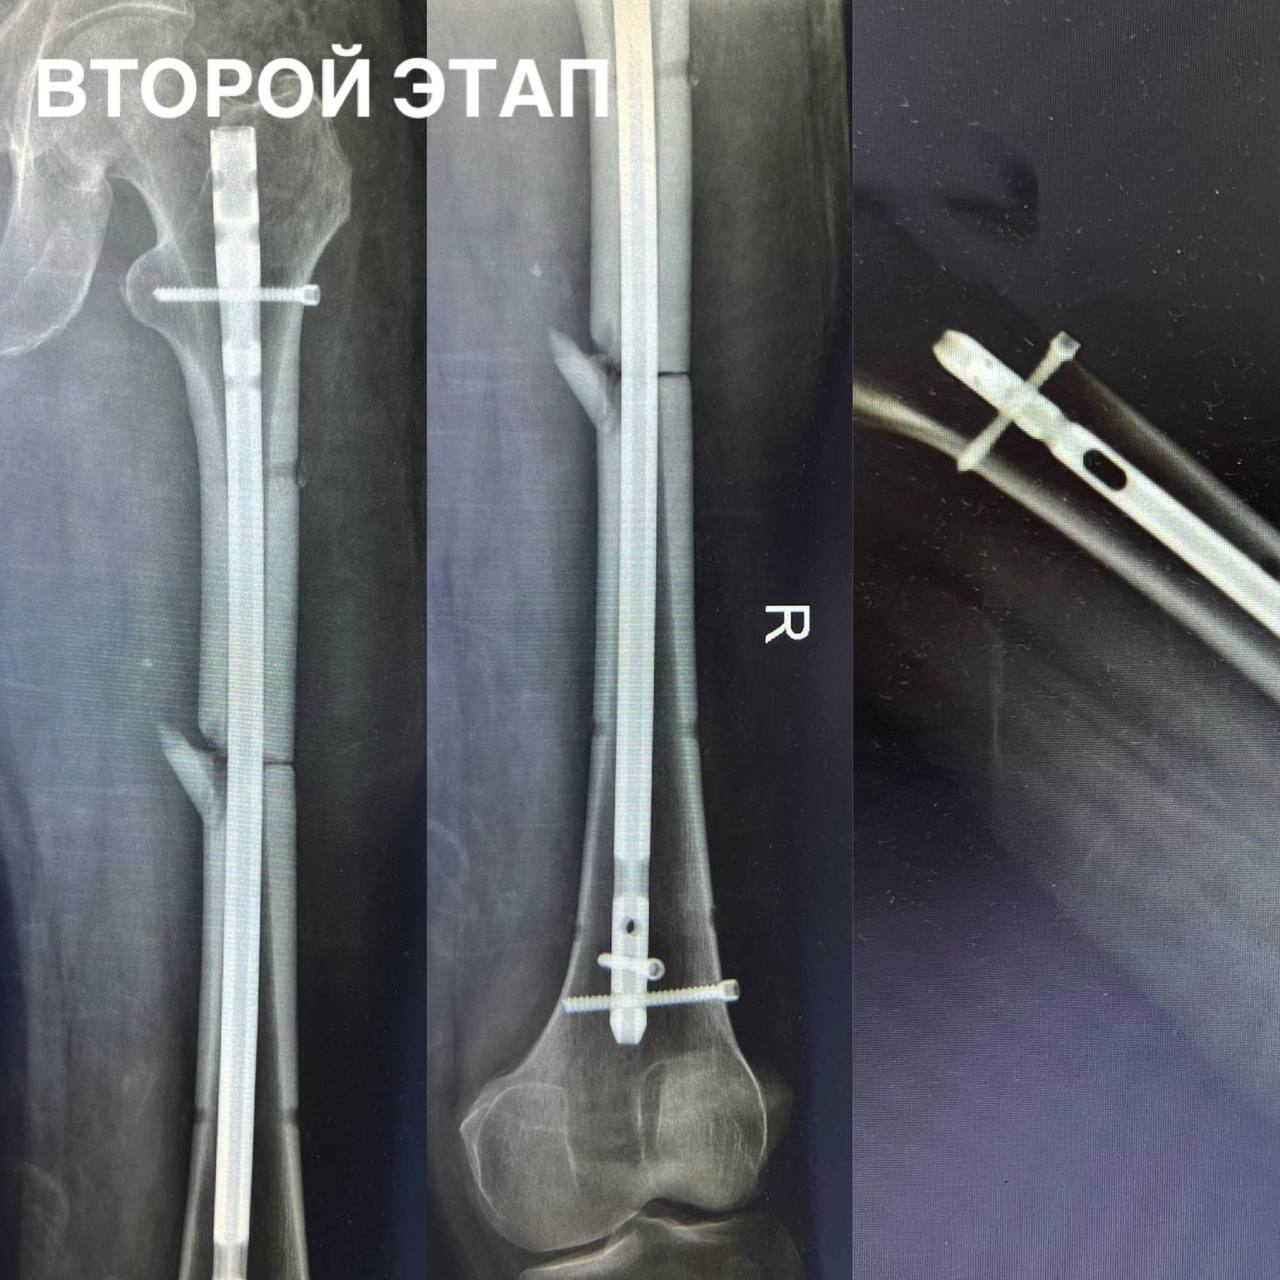

Врачи сразу взяли пациента в работу: обработали рану, стабилизировали состояние и провели сложнейший интрамедуллярный блокируемый остеосинтез. Эта методика позволяет надежно зафиксировать отломки и как можно раньше начать восстановление.